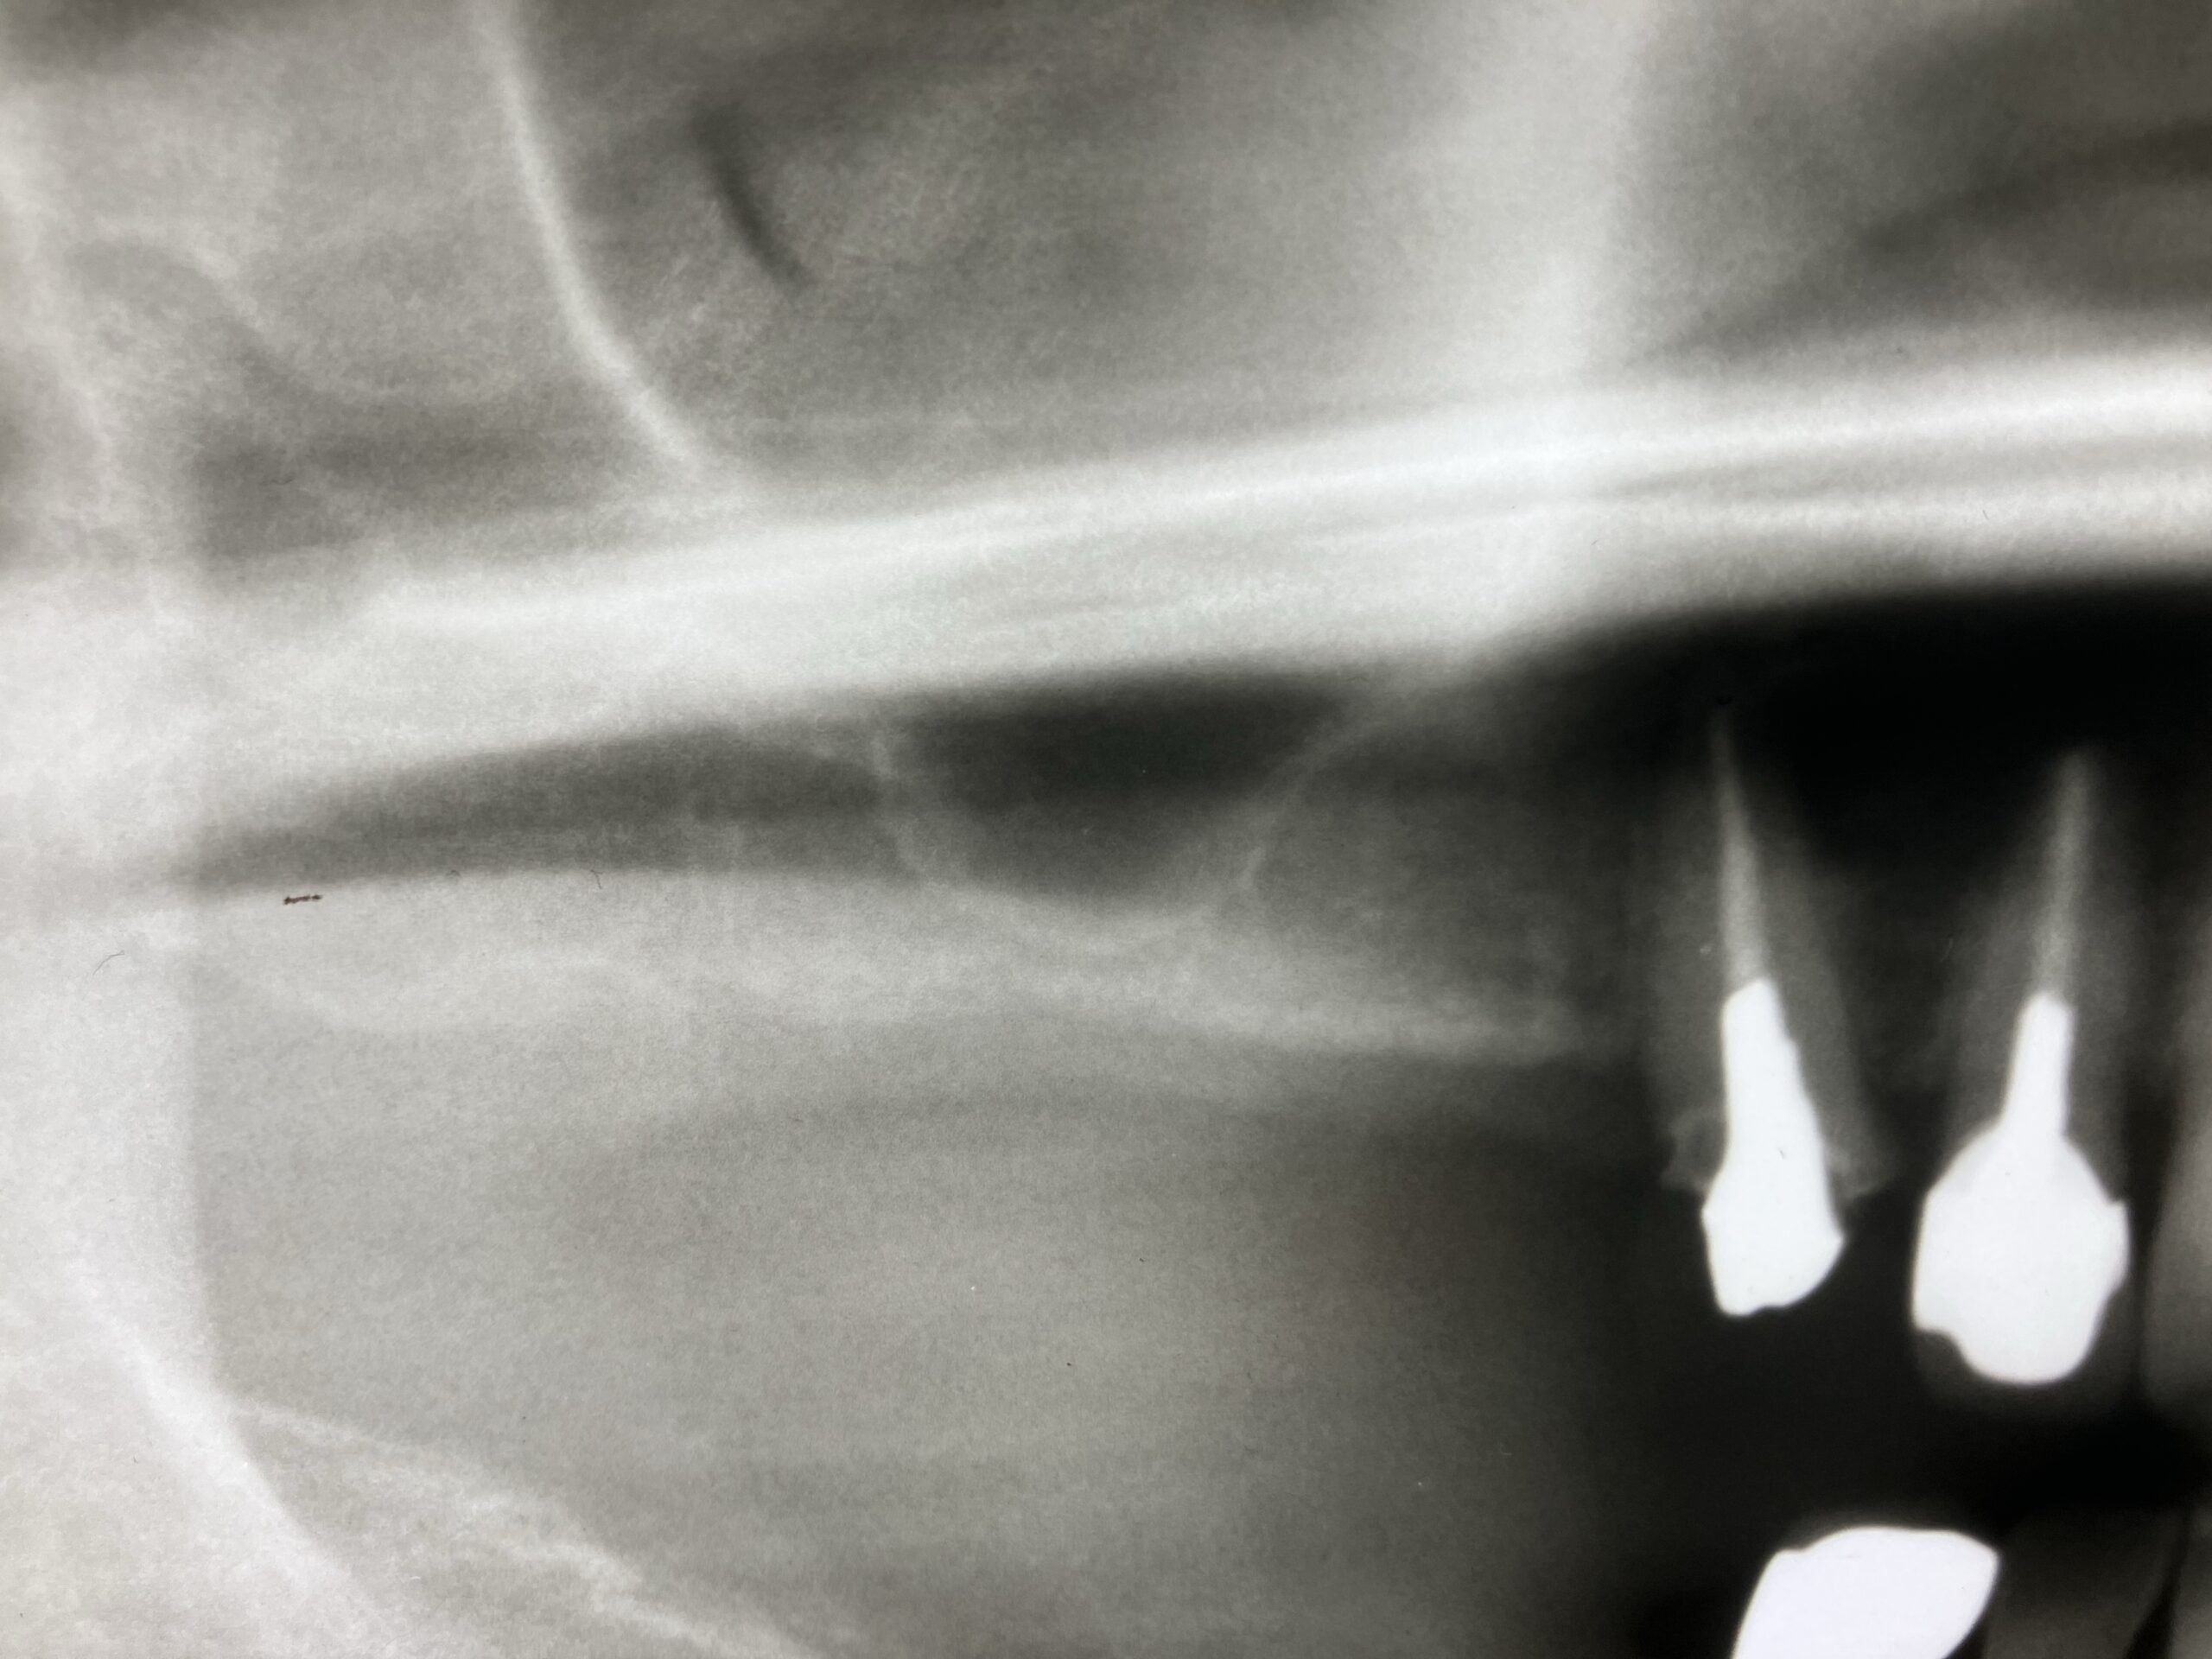

③ 上顎結節部(tuberosity)への埋入

臼歯さらに後方、結節部の海綿骨を利用

上顎洞を完全回避可能 フルアーチで有効

👉 デメリット

・骨質が軟らかい(D3〜D4)

・初期固定が難しい